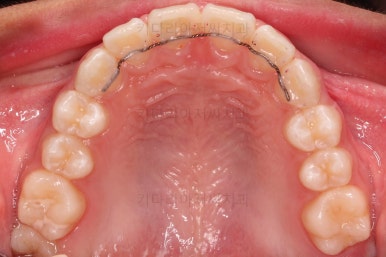

부산소아교정 초진 시 입안의 모습입니다.

윗니가 아랫니보다 많이 앞에 나와있고요.

심지어는 틈새가 벌어지기까지 했습니다.

윗니가 배열 되어있는 U자 형태(그릇 형태)가 아랫니보다 좁은 양상이고요.

이런 앵글씨 2급 부정교합에서는 아랫니가 윗니와 만나기 위해 솟구쳐서 과개교합(아래 앞니가 윗니 뒤쪽으로 깊숙히 올라가 있는 상태)이 나타나기까지 합니다.